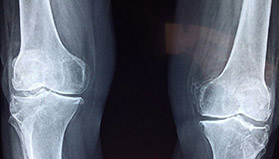

무릎에 발생한 골관절염